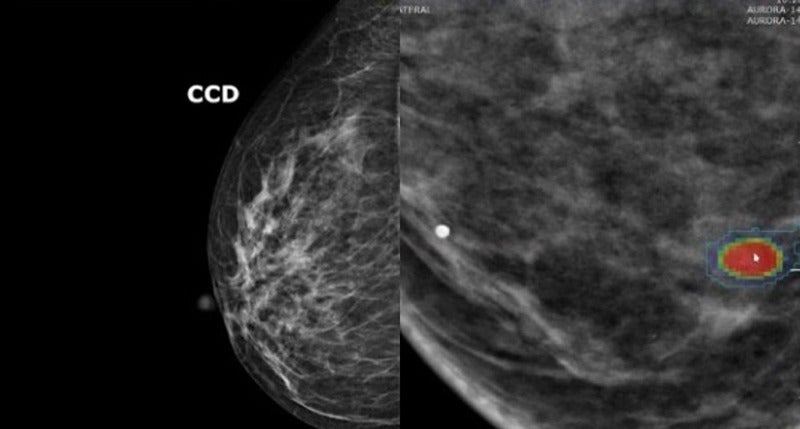

Por isso, Kuhl defende o rastreamento individualizado do câncer de mama. Afinal, a precisão da mamografia também varia significativamente de mulher para mulher: quanto mais denso o tecido mamário, maior o risco de desenvolver a doença – e pior a identificação pela mamografia. Muitas mulheres não sabem disso, conta a médica.

Ao contrário dos modelos de risco tradicionais, o algoritmo não requer informações sobre histórico familiar, genética ou estilo de vida. Ele calcula a probabilidade de câncer de mama exclusivamente a partir da mamografia e categoriza as mulheres em grupos de risco com base em limiares definidos.

A IA reconhece não apenas a quantidade de tecido glandular, mas também sua textura, o que é outro parâmetro para o risco de câncer de mama. “Apenas cerca de 10% das mulheres têm esse tecido glandular extremamente denso. A grande maioria das que desenvolvem câncer de mama e recebem um diagnóstico tardio têm tecido menos denso”, afirma Kuhl.